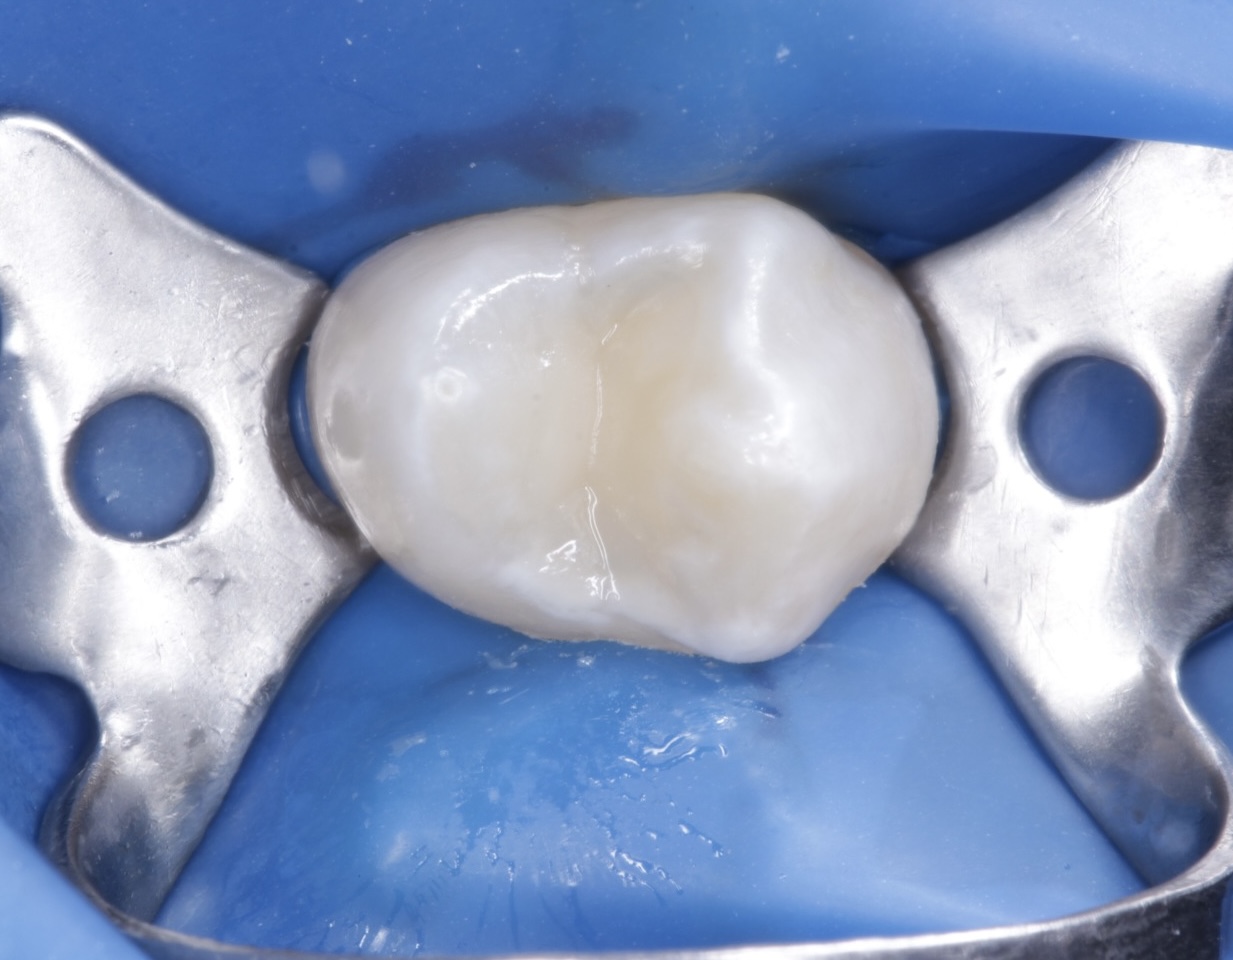

Бұрын

Бұрын

Кейін